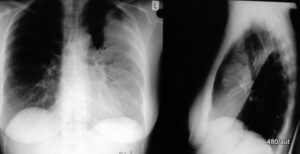

Abb. 6.02: Medizingeschichte. Vergleich unterschiedlicher Strahlung: 50 und 75 kV “Härte” bei einem Pneumothorax links und Wassereinlagerung der Lungen.

Dazu links unterexponiert, recht überexponiert.

6.02: Bei diesem Patienten liegt eine sehr kurzfristige Kontrolle vor. Es wäre unstatthaft, solche schlechten Aufnahmen absichtlich zum Vergleich anzufertigen. Beide kV-Zahlen sind nach heutiger Auffassung zu niedrig und würden zu Konsequenzen durch die ärztlichen Stellen führen.

Dieses medizingeschichtliche Beispiel ist gerade wegen der Qualitätsmängel didaktisch wertvoll.

Die 50 kV-Aufnahme links ist unterexponiert und daher zu weiß (hell im landläufigen Sinne). Das passiert bei niedrigen kV-Zahlen besonders leicht). Das zusätzliche Lungenödem kommt fast übertrieben zur Darstellung. Teilweise Auslöschung der Zwerchfellkonturen. Mantelförmiger Pneumothorax linksseitig.

Die rechte Aufnahme mit 70 kV ist überexponiert und daher zu schwarz.

Die Verdichtung der Lunge ist im Bereich der teilkollabierten linken

Lunge am stärksten ausgeprägt.

Problem solcher fehlerhafter Parameter: die Abgrenzung Artefakt( Pathologie und die Quantifizierung der Pathologie wird schwierig.